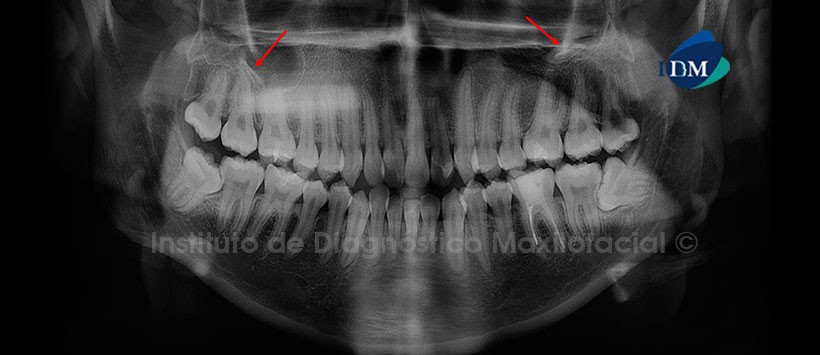

Paciente femenino de 20 años de edad que es referida para la evaluación de las piezas dentarias 14 y 15; por presentar dolor a la palpación a nivel de la tabla ósea bucal de la región de las piezas antes mencionadas. Sin embargo, en la radiografía panorámica no se evidencia cambios de la morfología habitual de la zona de interés. Por otro lado, llama la atención la presencia de imágenes de radiodensidad cálcica y de forma irregular, proyectadas sobre las paredes basales de los senos maxilares compatibles con Antrolitos (Fig. 1).

Las calcificaciones en tejidos blandos de la región bucomaxilofacial son comúnmente observados en las distintas técnica de imagen del campo estomatológico. A la evaluación radiográfica, los antrolitos se encuentran proyectados sobre la pared basal del seno maxilar, tienen límites definidos, con forma lisa o irregular; en su interior pueden observarse imágenes radiopacas desde imperceptibles hasta muy marcadas, homogéneas o no, que en algunos casos adoptan formas de láminas radiopacas.